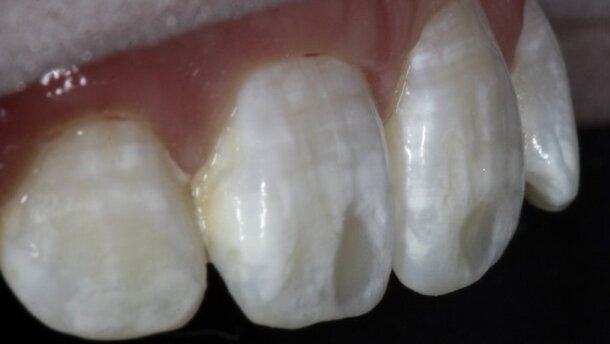

27-letnia pacjentka zgłosiła się do lekarza dentysty z powodu białych plam na górnych przednich zębach (Ryc. 1 i 2). Kilka lat wcześniej inny dentysta podjął próbę eliminacji najbardziej intensywnych zmian przez ich usunięcie wiertłem i wykonanie wypełnień kompozytowych. Wskutek użycia kompozytu o nieprawidłowym stopniu jasności, u pacjentki pojawiły się 2 ciemne plamy na siekaczach przyśrodkowych. Pacjentka próbowała wcześniej stosować domowe wybielanie zębów w celu wyrównania koloru pozostałych plam, jednak bez powodzenia. Całkowity zasięg białych plam i wypełnień kompozytowych można zobaczyć na rycinie 3 – zdjęciu wykonanym z kołowym filtrem polaryzacyjnym, który eliminuje odbijanie promieni świetlnych od powierzchni (www.emulation.gr).

Efekt uzyskany po spolimeryzowaniu można zobaczyć na rycinie 9. Uzyskano znaczną redukcję białych plam, chociaż nadal pozostały ubytki szkliwa związane z wcześniejszymi wypełnieniami (Ryc. 10). Ubytki te wypełniono materiałem kompozytowym. Nie było potrzeby dodatkowego przygotowywania szkliwa, ponieważ żywica Icon pozwala na adhezję dzięki własnej warstwie inhibicji tlenowej. Wybrano materiał kompozytowy z mikrowypełniaczem B1 Renamel (Cosmedent), który naniesiono płaskim artystycznym pędzelkiem w celu uzyskania gładkiego przejścia do naturalnej tkanki zęba. Przed zdjęciem koferdamu przeprowadzono ostateczną polimeryzację wypełnień kompozytowych i żywicy Icon po ich pokryciu gliceryną w celu usunięcia efektu powierzchownej warstwy inhibicji tlenowej.

Pacjentka zgłosiła się na wizytę kontrolną po 2 tygodniach. Na rycinach 11-14 widoczny jest doskonały efekt, w tym zmniejszenie białych plam na zębach, na zdjęciach z kołowym filtrem polaryzacyjnym, co wskazuje na pełen zakres redukcji białych plam (Ryc. 11).